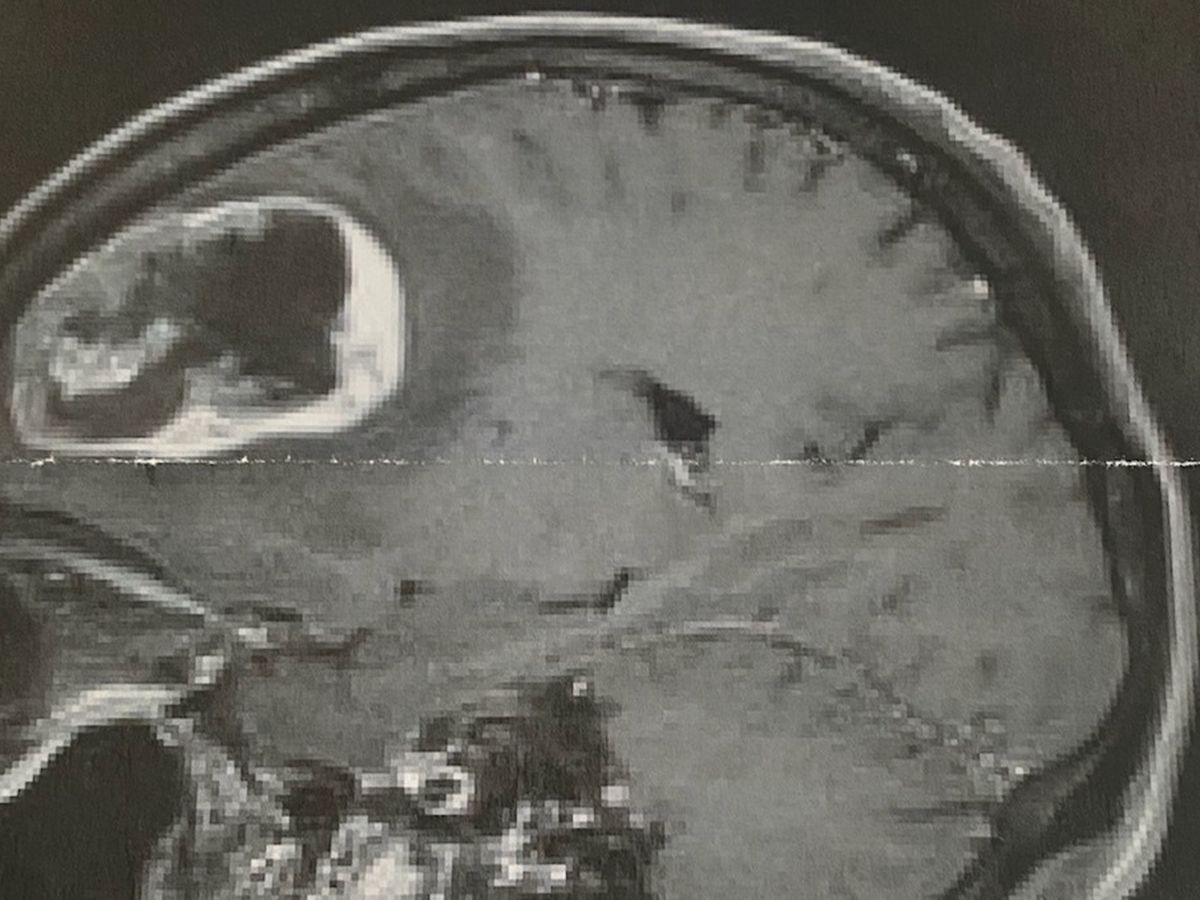

Pictured above is an MRI showing the tumor in our dads (Robert Williams aka Bob) brain.

Now he's in the hospital. An MRI showed this orange-sized growth in his frontal lobe. Yes. The size of an orange. It's that big, and it needs to go.